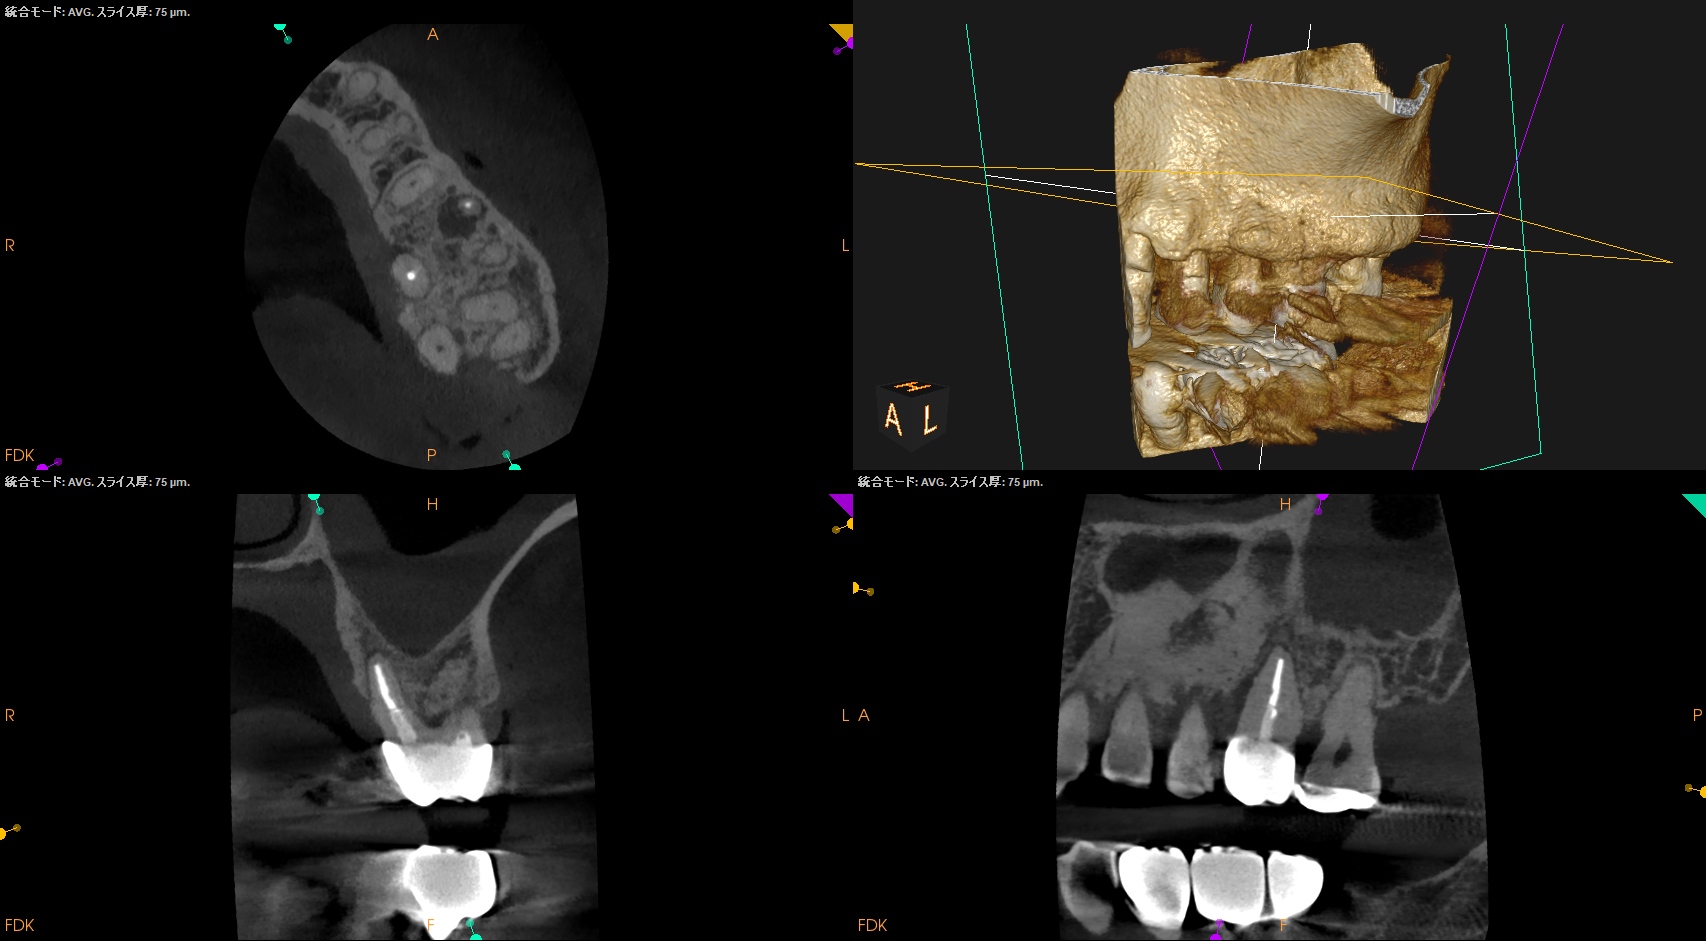

Pre-op Endo Test(2026.3.6)

MB

DB

P

MBの根尖病変が大きくなり上顎洞に穿孔している。

歯性上顎洞炎の可能性がある。

そしてMB2と思しきものはあるが、それが非外科的歯内療法で穿通する保証もない。